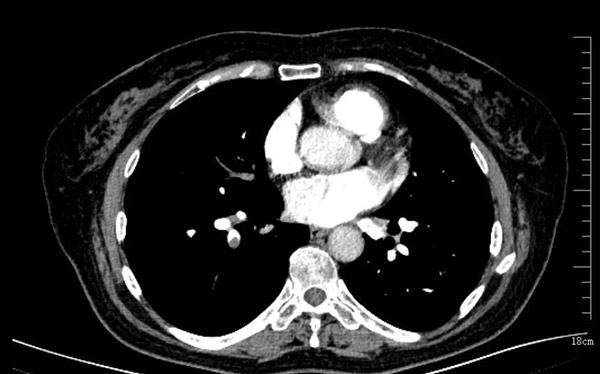

近日,沈阳市第十人民医院(沈阳市胸科医院)呼吸四病区迎来了一位辗转就医1年多的患者。62岁的金女士,平时身体很好,肺炎后总是觉得胸闷气短。她先后去了很多家医院做了肺CT基本正常、血压不高、心电图也没有明显问题。她的邻居和朋友告诉她需要多休息。但是1年多过去了,金女士总是觉得喘气喘不到底,活动后胸闷气短,到底是什么问题呢?呼吸系统及肺血管疾病专家于秀丽主任接诊后,给金女士做了心脏彩超发现她的肺动脉高压高达70mmHg,而正常人心脏彩超肺动脉压力一般不超过37mmHg。于是立刻给她安排肺动脉增强CT及右心导管检查。经肺血管造影及肺动脉测压,发现金女士的肺动脉的压力远远超过正常人,并且在她的肺动脉血管内有较多血栓附着。这些病灶导致她呼吸困难明显,活动耐力下降。最后经过医务人员的及时诊治,金女士的气短胸闷明显好转。

肺动脉高压是一种常见的血液动力学异常状态,涉及多学科、多系统,诊疗难度大,死亡率高,基层认识不足的疾病。目前肺动脉高压临床分为五大类。包括动脉性肺动脉高压、左心疾病所致肺动脉高压、肺病和(或)低氧所致肺动脉高压、肺动脉阻塞所致肺动脉高压、机制未明和(或)多因素所致肺动脉高压。肺血管疾病诊治中需常规完善右心导管术并完善相关检查用于筛查并明确危险因素。而且怀疑肺动脉高压应尽早转诊至诊疗中心。